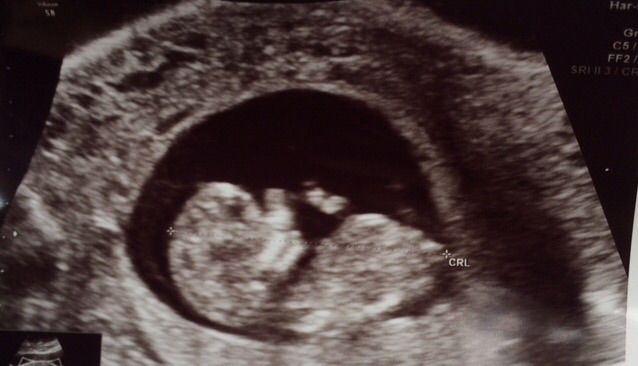

Appointment went well today! Baby continues to grow and has a strong heartbeat. My ob was great too- said that I can come in every 2 weeks instead of every 4 weeks (at least for the next few appointments) so that I don't get so nervous between appointments. I included a picture of our little one- a little blurry, but a baby!! Crazy how small it is!!

We had a great appointment. We are at 8w3d. I cried as soon as we heard the heartbeat. I'm so relieved. I go back in two weeks for a feel good check up. From here on out it's uncharted territory. I'm glad to be past my milestone mark.